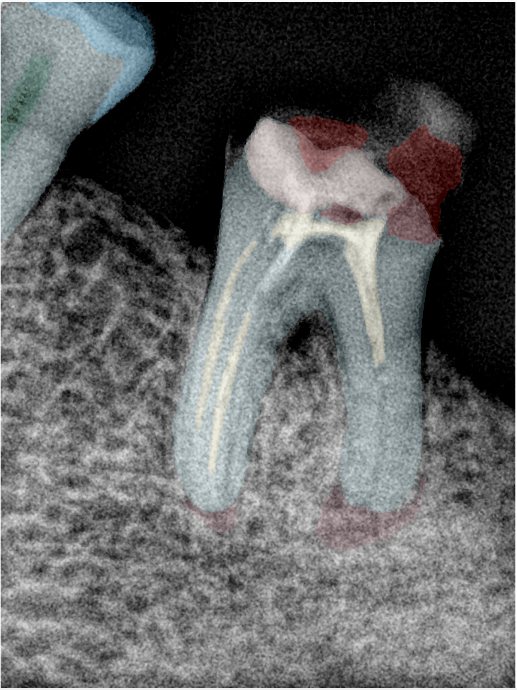

CR/DR 牙齿分割阶段记录

当前进展

- 完成了 CR/DR 牙齿相关分割训练

- 当前结果已经达到阶段预期,但仍有细节问题需要继续处理

相关测试

遇到的问题

- 训练过程中出现过 mask 下移问题

- 部分结果会出现 box 填充异常

- mask 边缘仍然有比较明显的锯齿感

参考

第二版算法问题测试

Updated: 2026-04-13(更新日期)

| 第一版 | 第二版 | 是否解决 | |

|---|---|---|---|

![]() | ![]() ![]() 边角识别有问题 龋齿识别不全 牙髓识别不全 | ![]() | 解决 |

![]() | ![]() 边角识别有问题 识别信息有误 自查(牙冠识别不全) | ![]() | 解决 |

![]() | ![]() ![]() 边角识别有误 大范围填充识别遗漏 | ![]() | 解决 |

![]() | ![]() 识别信息不全 | ![]() | 解决 |

![]() | ![]() ![]() 边角问题 牙胶识别不全 牙冠识别不全 | ![]() | 解决 |

![]() 换图片 | ![]() | ![]() 牙冠部分稍微白了一些就识别成小范围修补,部分判断异常 | 部分解决,修复类略敏感,牙冠部分稍微白了一些就识别成小范围修补,部分判断异常。 |

![]() | ![]() ![]() 牙冠识别不全 牙髓不全 根尖炎龋齿识别有误 | ![]() | 解决 |

![]() | ![]() | ![]() | 解决 |

![]() 换图片 | ![]() | ![]() | 解决 |

![]() | ![]() 牙冠识别有误 | ![]() | 解决 |

![]() 换图片 | ![]() ![]() 边角识别有误 | ![]() 修复类敏感 | 部分解决,图像过白,导致修复类判断异常。 |

![]() 换图片 | ![]() 牙冠识别不全 | ![]() 修复类敏感 | 部分解决,图像过白,导致修复类判断异常 |

结论:修复类出现了不鲁棒的情况,后续需要加入轮廓的扩充数据进行增强。